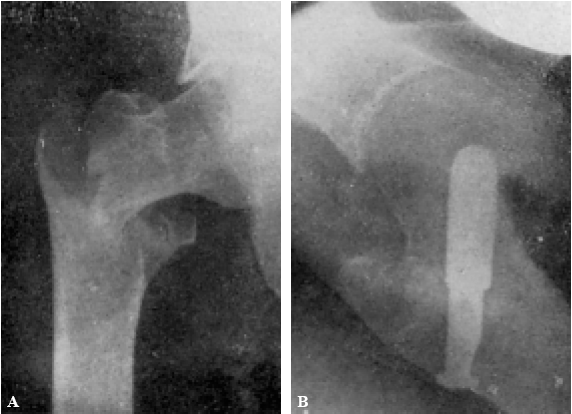

Con buena técnica, todos los resultados son favorables, a pesar de que al cabo de algunos años exista un grado más o menos acentuado de artrosis (véanse la observación núm. 4, fig. 7., A y B, y la observación núm. 9, fig., 8. A, B y C), que corresponden a los dos enfermos que hace más tiempo que están operados, y que en la actualidad aún viven.

Figura 7. A: obs. núm. 4. Enfermo de sesenta y cuatro años, operado en noviembre de 1935. La situación del clavo puede aceptarse como buena (ligeramente craneal). B: obs. núm. 4. Radiografía del mismo enfermo de las dos figuras anteriores, practicada en la actualidad (julio de 1943). Artrosis manifiesta. La cabeza del fémur tiende a aplastarse. Deambulación perfecta.

Figura 8. A: obs. núm. 9. Enferma de cuarenta y cinco años, operada en enero de 1937. El clavo procedía del cadáver de la observación mencionada como fracaso número I, y presentaba unos ligeros depósitos de herrumbre. La situación del clavo es buena. B: obs. núm. 9. El mismo caso de la figura anterior. En proyección lateral también es perfecta la situación del clavo. Éste tuvo que ser extraído a los siete meses de intervenida la fractura, a causa de una persistente supuración. C: obs. núm. 9. Radiografía del caso de las dos figuras anteriores, practicada en julio de 1943. Artrosis muy ligera. El cuello del fémur parece muy estrechado, pero esta deformidad también puede apreciarse en la figura B. Deambulación perfecta.